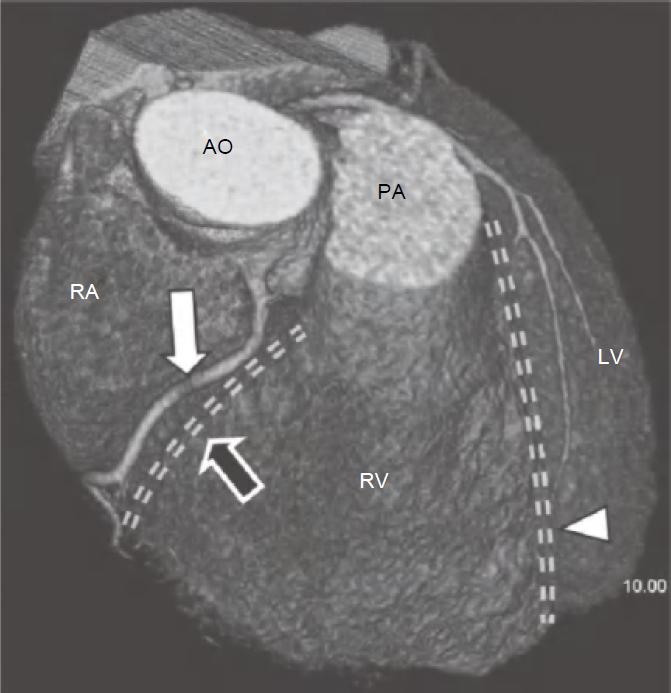

通常,RCA自右冠窦前方发出后在右房室间沟(RAVG)内向前然后向下走行,到达心脏的后方(图13-3及图13-4)。

图13-3 RCA(白箭)起自主动脉的前部,并沿RAVG(黑箭)走行。图中还可见位于前室间沟内(箭头)的LAD

AO.主动脉;PA.肺动脉;RA.右心房;RV.右心室;LV.左心室